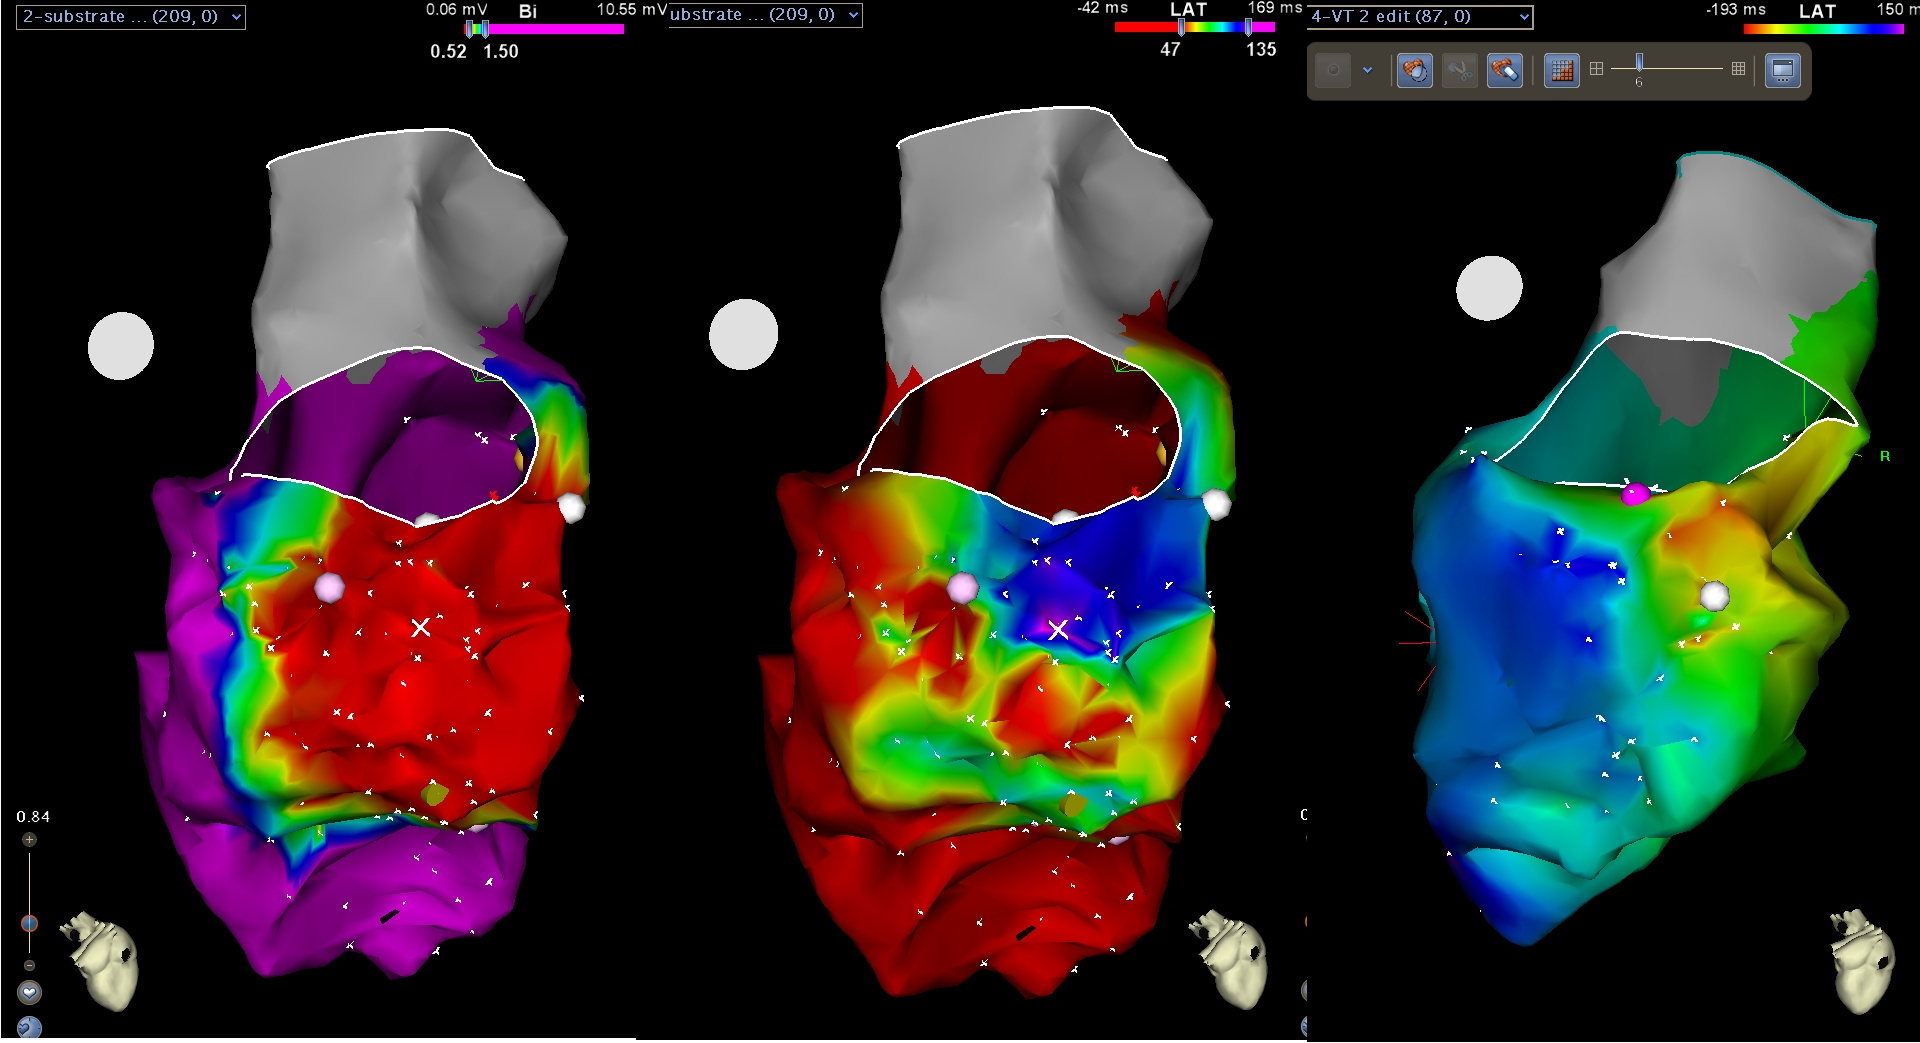

Electrograms of abnormal substrate

Low voltage zones

Cut-offs

Voltage cut-offs for endocardial signals 0.5 - 1.5 mV

• Apply to both RV and LV

• Both cut offs are flexible

• Higher voltage cut off (2.5) in patchy scar (early reperfusion)

• Patient specific cut offs ?

• Uniform, homogenous lvz with rest of myocardium not changing color (upper cut off)

• See channels / isthmus - lower cut off

Rapid, partial activation map

scar_channel.jpg

Ablating channels to eliminate LP

lat_percolation.jpg